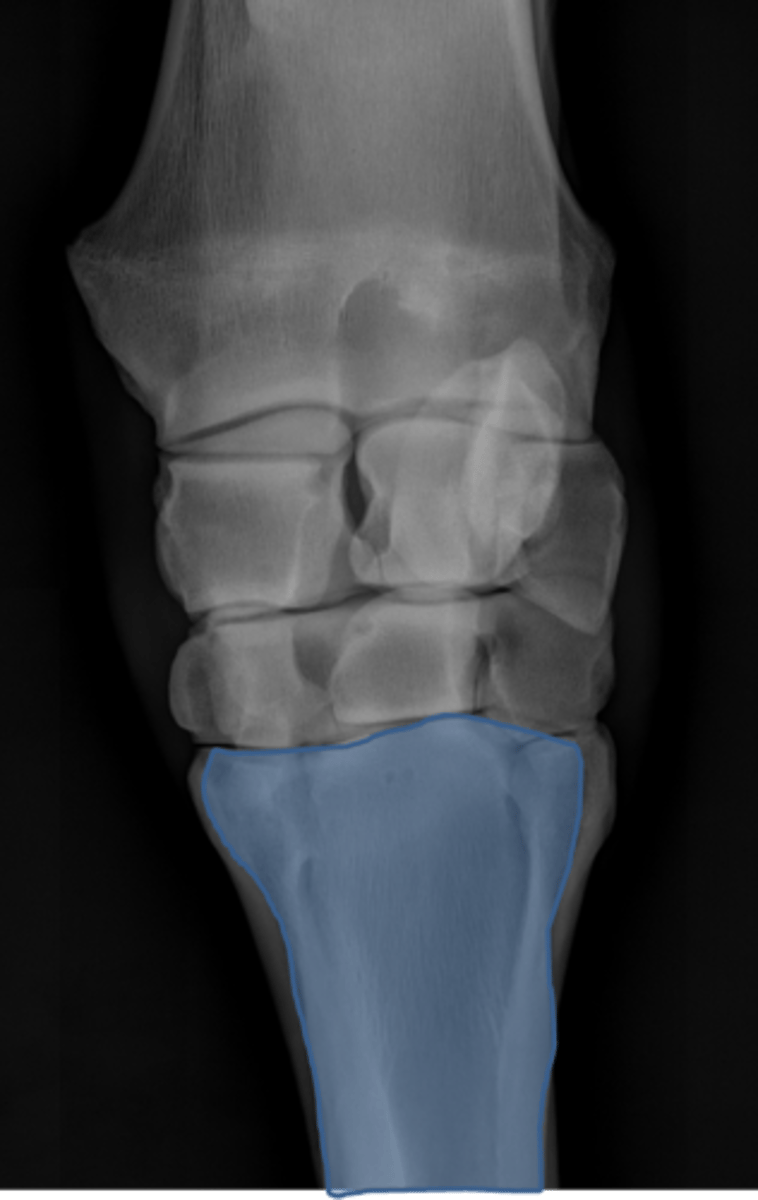

Carpus, DP

ID joint and view

Accessory carpal bone

Radial carpal bone

Intermediate carpal bone

Ulnar carpal bone

Second carpal bone

Third carpal bone

Fourth carpal bone

Second metacarpal (medial splint)

Third metacarpal

Fourth metacarpal (lateral splint)